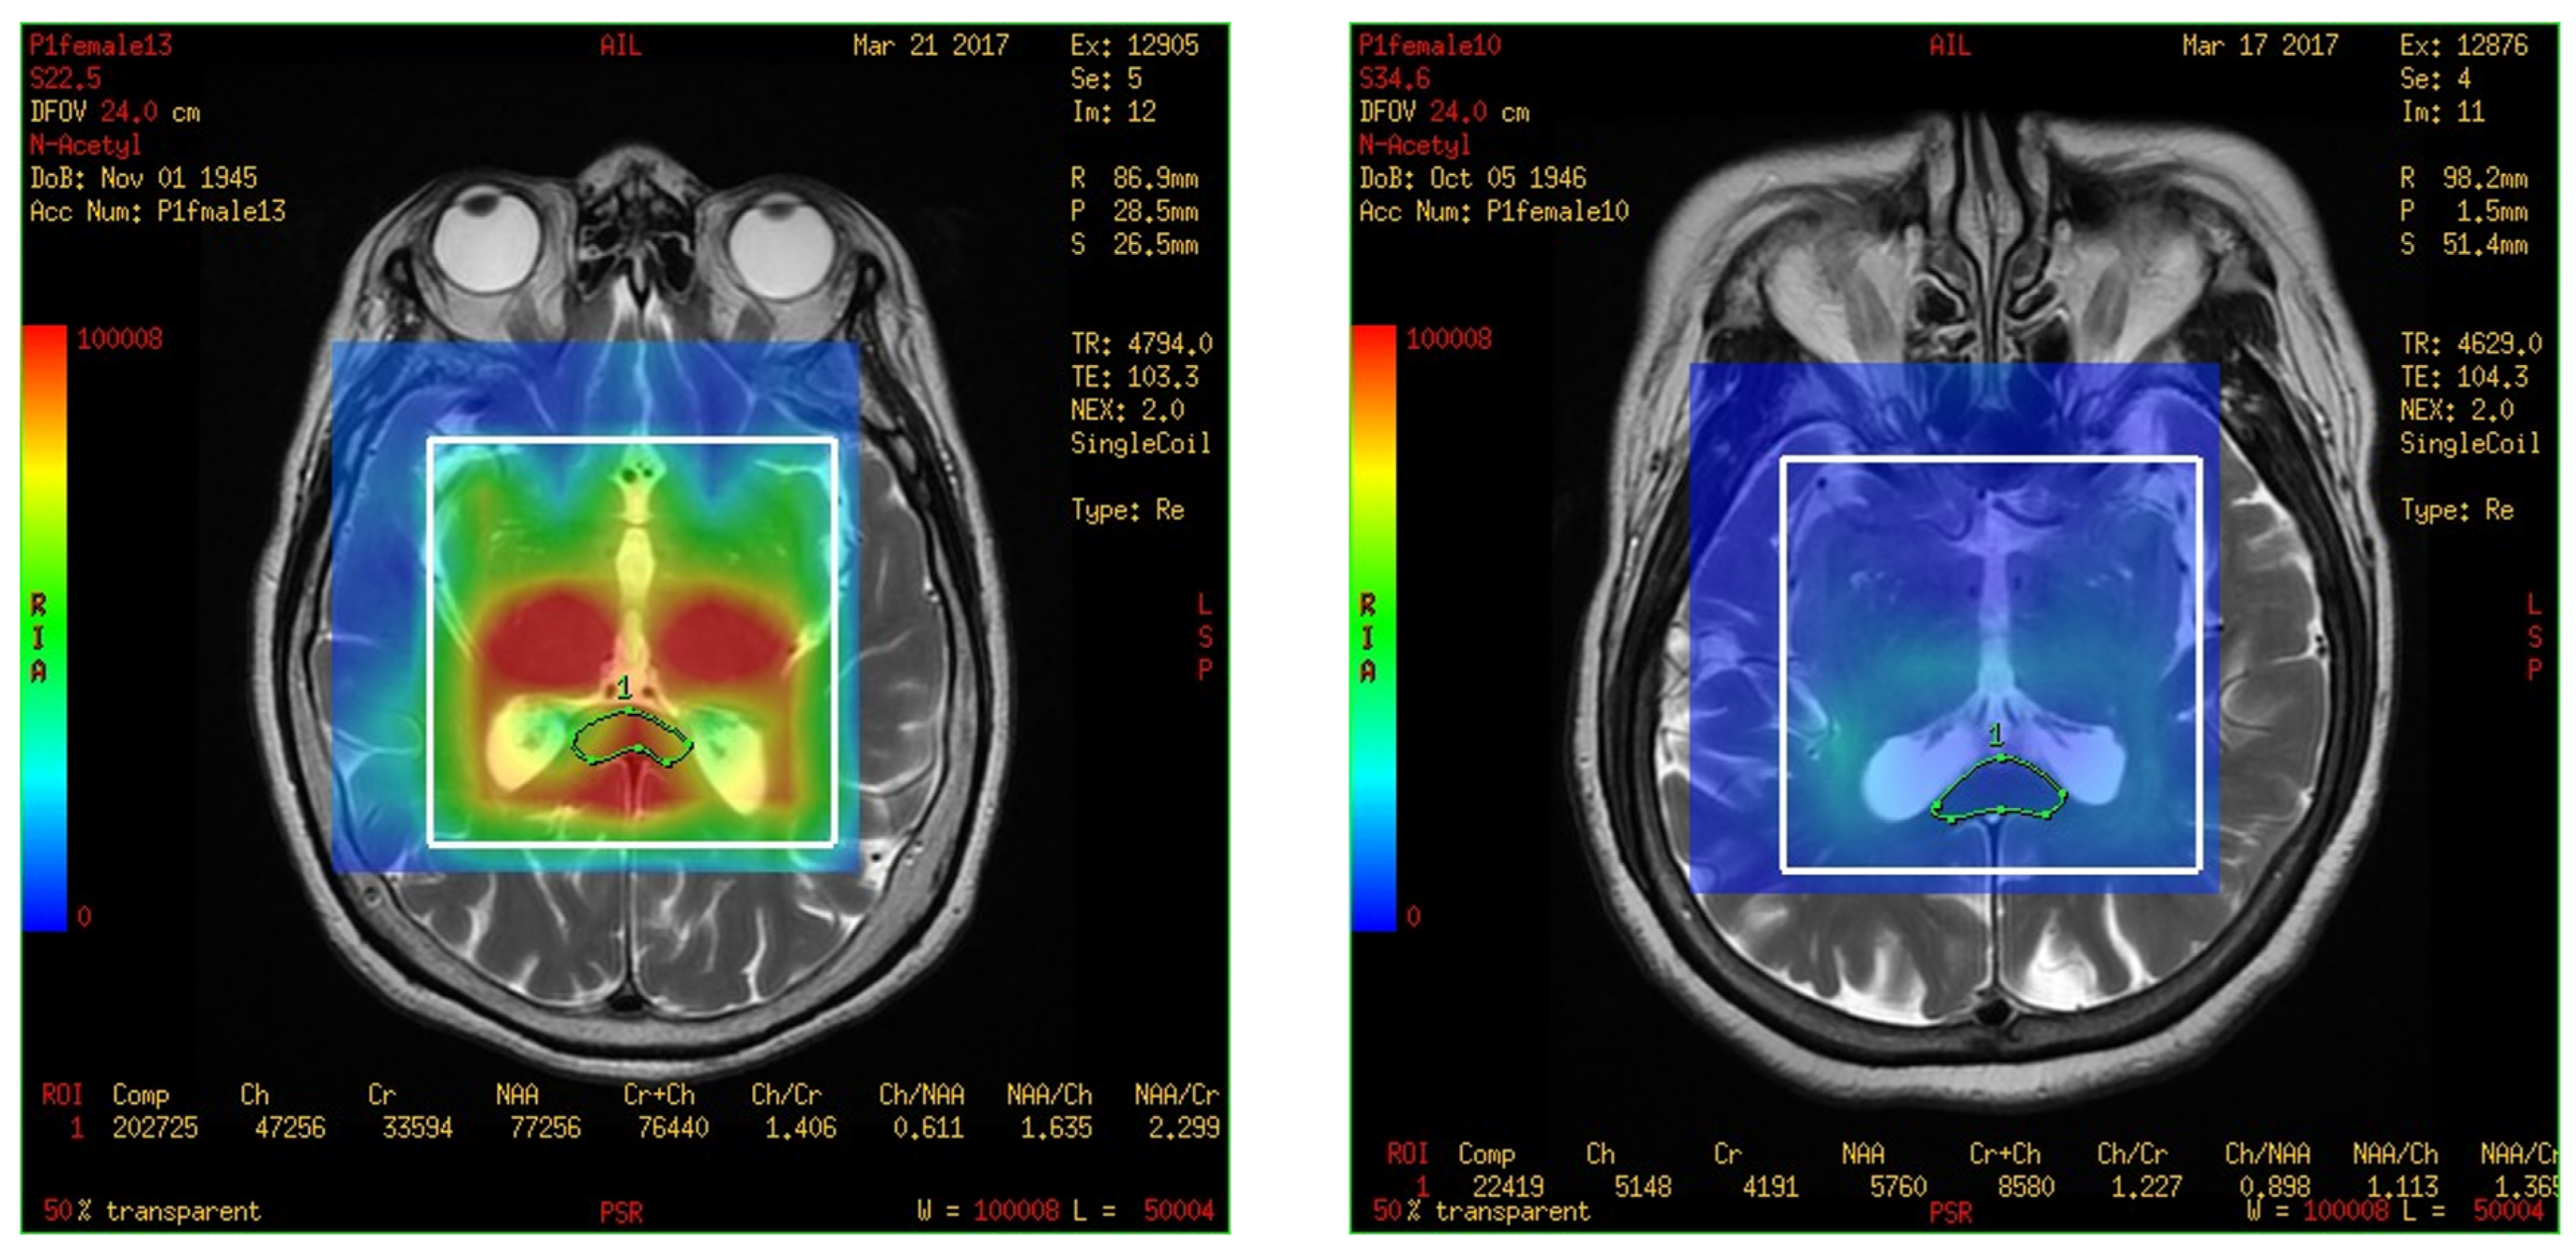

On comparing the metabolites in the corpus callosum between the MCI and control group, the ratio of normal Cr between two groups compared as follows: NAA/Cr (0.778 ± 0.333 vs. 2.506 ± 1.648, p = 0.020), MI/Cr (0.062 ± 0.056 vs. 0.222 ± 0.136), and the level of signal intensities of Cr (4200 ± 2100 vs. 16,200 ± 11,800, p = 0.02) were significantly lower in the MCI group (Table 3). The result was easily visible in the color map of the MRS with 3D-CSI. For example, the MRS with 3D-CSI color map of NAA showed a red color (high signal) in the corpus callosum area of the control group, while it showed a blue color (low signal) in the corpus callosum area of the MCI group (Figure 4). For the levels of signal intensities of Cho/Cr, there was a trend of lower intensity at the corpus callosum in the MCI group compared with the control group, but without significant difference.

Figure 4.

Magnetic resonance spectroscopy with three-dimensional chemical shift images color map of N-acetyl aspartate. The left figure shows red color (high signal intensity) in the corpus callosum area (green markup) of control group. The right figure shows blue color (low signal intensity) in the corpus callosum area (green markup) of mild cognitive impairment group.